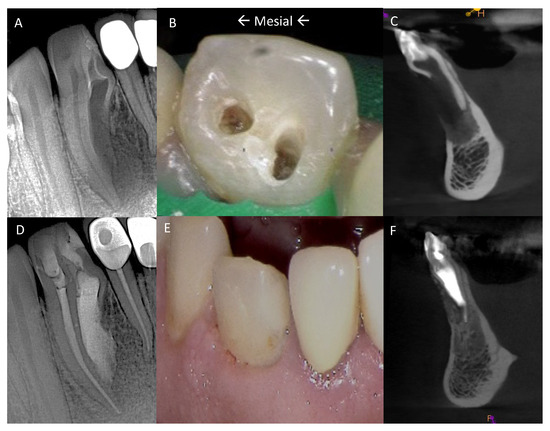

2.1. Pretreatment Planning